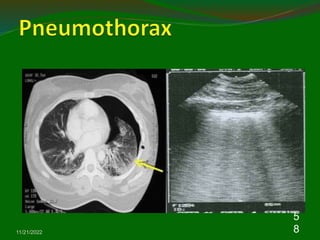

5. Pneumothorax

Chest US may be help in the diagnosis of

pneumothoraces.

Normal parietal and visceral pleura slide over each other

during respiration and a pneumothorax is suspected

when this ‘Gliding sign’ is absent in chest US

A recently published systemic review, chest US had a

sensitivity of 90.0% and a specificity of 98.2% .

The confirmation of lung gliding has a 100% negative

predictive value for the absence of pneumothorax .

The use of M-mode can also objectify the presence or

absence of lung gliding

Pneumothorax

Normal Lung

M-mode for sliding - normal

straight

speckled